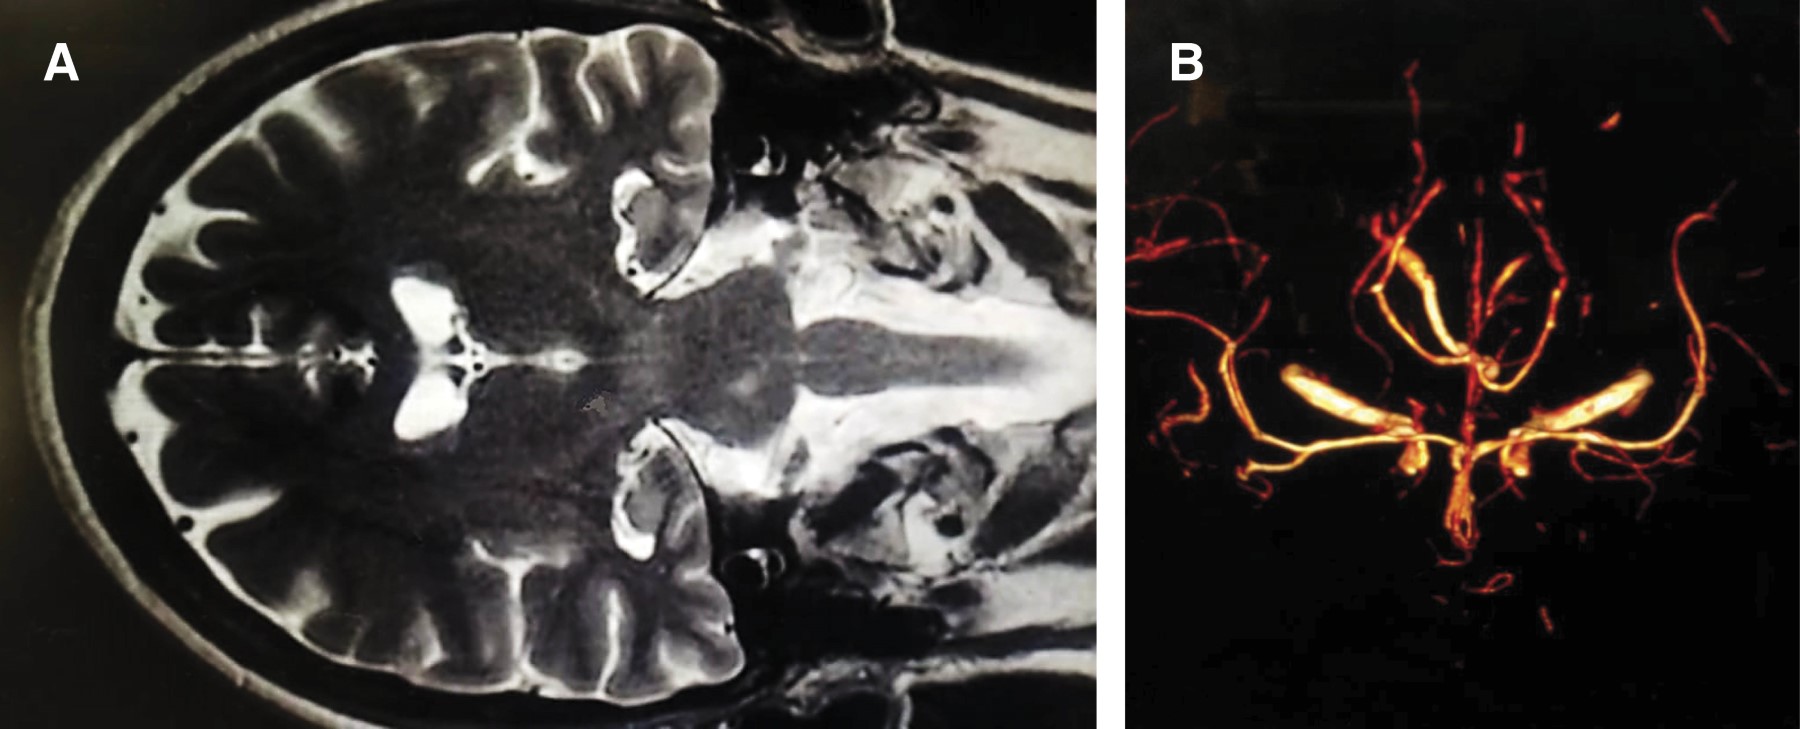

Mujer de 30 años con antecedente de cesárea bajo anestesia epidural en septiembre de 2022. A los cuatro días de su cirugía inicia con lumbalgia intensa, posteriormente cefalea holocraneal con intensidad 10/10 intermitente, posteriormente se volvió persistente, se agregó rigidez cervical, así como acúfenos y fotofobia. Ingresó a hospitalización con realización de punción lumbar, con 9 leucocitos, glucosa de 20 y proteínas de 198 mg. Se decidió instaurar tratamiento con anfotericina B calculada a 5 mg/kg y voriconazol 300 mg, ácido acetilsalicílico 150 mg al día, así como esteroide sistémico. La paciente presentó remisión de los síntomas a las dos semanas del tratamiento. Se le realizaron punciones lumbares seriadas con hiperproteinorraquia e hipoglucorraquia, completando dos meses de tratamiento hasta su egreso. La imagen por resonancia en esta paciente mostró disminución del calibre de las ramas distales de la arteria cerebral media izquierda (Figura 3), sin embargo, la PCR para Fusarium fue negativa.

Figura 3